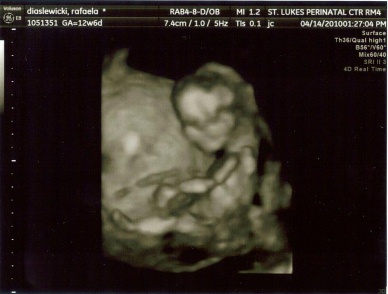

And this is my story! I was lucky enought to get a 3D pic of the little guy!!!!! Now.....back to my original name....lol Image Attachment(s):